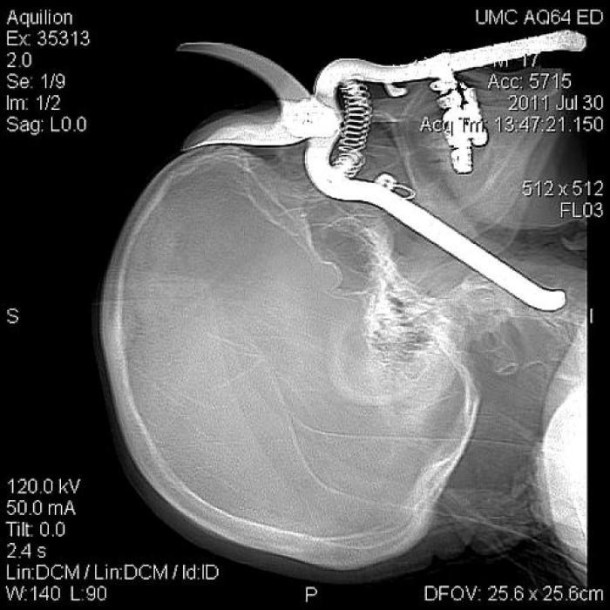

33 radiographies qui prouvent que les gens font des choses douteuses avec leur corps !